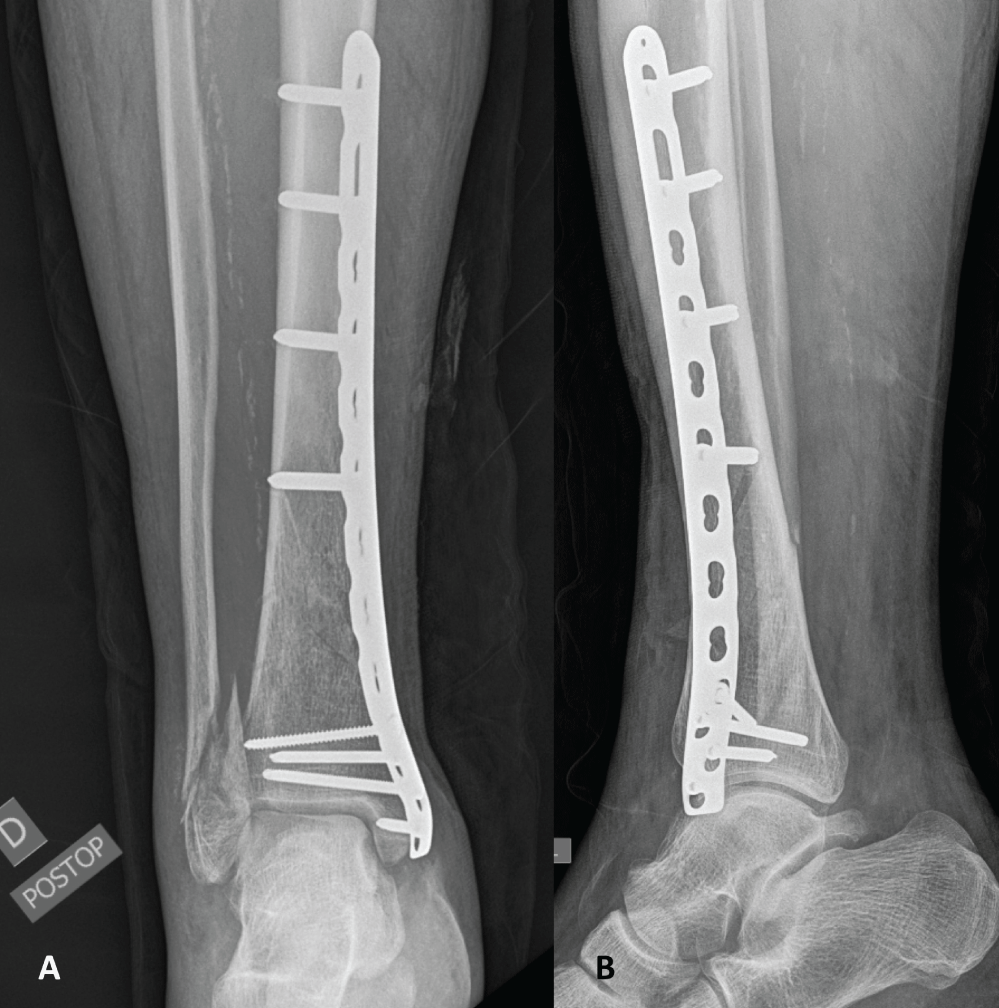

The second step consisted of the diaphyseal tibia fracture fixation using a standard MIPO technique. A 3 cm incision above the medial malleolus was made and a low profile anatomically pre-contoured 3.5/4.5 mm locking compression plate (LCP; Synthes®, Oberdorf, Switzerland) was subcutaneously inserted in a retrograde fashion. A 3 cm medial incision was made over the proximal end of the plate, 2 cm posteriorly to the anterior crest of the tibia. Reduction was obtained indirectly with manual traction of the limb under fluoroscopic guidance and confirmed by direct visualization through the anterolateral incision. After provisional fixation with 1.6 mm Kirschner wires, the plate was fixed proximally and distally with the appropriate locking screws. Due to swollen soft tissues over the lateral malleolus and poor skin quality, distal fibular fixation was postponed. The surgical wounds were closed and dressed in the customary manner. Upon operating room discharge, the foot was well perfused and pedal pulse was present on the operated side. Postoperative radiographs showed adequate fracture reduction (Figure 4).

Figure 4: Plain anteroposterior (A) and lateral (B) radiographic views following distal tibia fixation revealing adequate reduction. View Figure 4